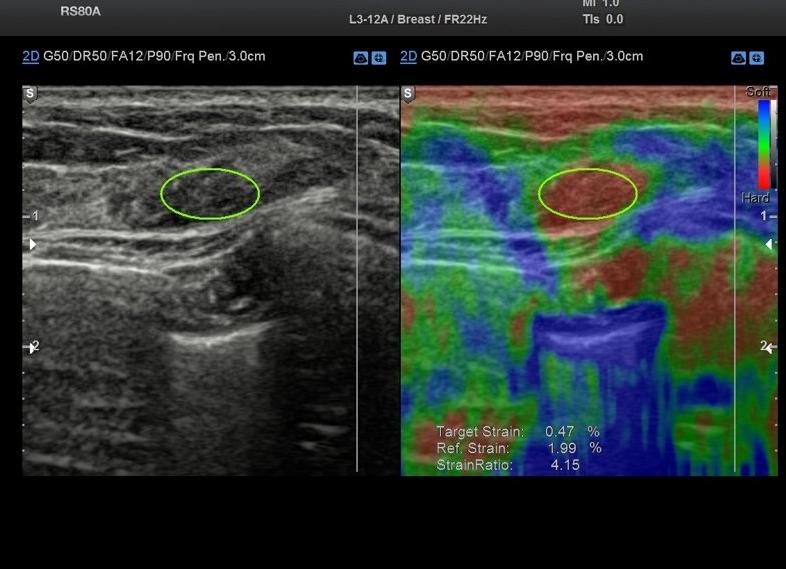

Две секции экрана сканера представляли стандартный В-режим и соноэластографическую интерпретацию. Эластичность тканей определялась и отображалась определенными цветами на обычном экране В-режима. Для оценки эффективности соноэластографии были выделены качественные и количественные диагностические критерии. Качественная оценка заключалась в анализе распределения эластичности тканей молочной железы, к количественным критериям относился коэффициент деформации, то есть степень деформации образования молочной железы по сравнению с неизмененными окружающими тканями. Первоначально производилась оценка образования в стандартном В-режиме. После активации методики эластографии выбиралась зона интереса в зависимости от размера и положения образования. В зависимости от степени плотности образования и инфильтрации окружающих тканей эластографические изображения классифицировали следующим образом (рис.1).

Первые три типа эластограмм относятся к доброкачественным образованиям (рис. 1а,1б,1в), четвертый и пятый типы — к злокачественным (рис. 1г, 1д). Нами получено еще два типа изображения: трехслойный тип — характерный для жидкостьсодержащих структур и мозаичный тип с участками зеленого и красного цвета (рис. 1е, 1ж). Коэффициент деформации рассчитывался автоматически с помощью программного обеспечения ультразвукового сканера. Данное измерение являлось не абсолютной, а относительной сравнительной величиной и показывало во сколько раз образование плотнее, чем жировая ткань.

Результаты ЭГ у больных РМЖ отличались от результатов у пациентов с доброкачественными образованиями за счет более высокой плотности узлов и инфильтрации окружающих тканей. При злокачественных образованиях в 78,6 % определялся четвертый и пятый тип эластограммы. В то время как, при доброкачественных заболеваниях в 94,5 % определялся первый, второй, третий, шестой и седьмой тип эластограммы. При анализе ЭГ в четвертом типе эластограммы образование имело отображение в виде гомогенного плотного узла, окружающие ткани сохраняли нормальные параметры эластичности. Данный тип достоверно чаще был характерен для солидных, отграниченных карцином (р

На экран монитора результаты отображаются в виде цветных снимков. Зеленый оттенок означает, что ткани здоровые, красный – присутствуют промежуточные зоны, синий – ткани имеют уплотненную структуру.

При наличии ярко-синих участков можно практически со 100% уверенностью утверждать, что опухоль имеет злокачественный характер. Однако на основании только этих показателей ставить точный диагноз нельзя.